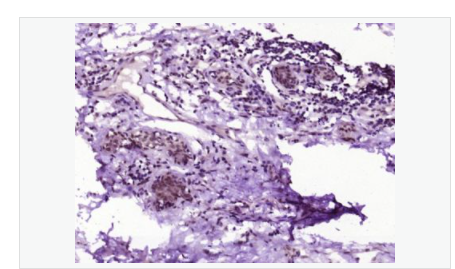

| 產品應用 | WB=1:500-2000 ELISA=1:5000-10000 IHC-P=1:100-500 IHC-F=1:100-500 IF=1:100-500 (石蠟切片需做抗原修復) not yet tested in other applications. optimal dilutions/concentrations should be determined by the end user. |

| 產品介紹 | Acts as a growth inhibitor. Can activate TP53/p53, causes G1 arrest and collaborates with CDKN2A to restrict proliferation, but does not require either protein to inhibit DNA synthesis. Redistributes CDKN2A into the nucleoplasm. Involved in maintaining chromosomal stability. There are two isoforms. Function: Acts as a growth inhibitor. Can activate p53/TP53, causes G1 arrest and collaborates with CDKN2A to restrict proliferation, but does not require either protein to inhibit DNA synthesis. Redistributes CDKN2A into the nucleoplasm. Involved in maintaining chromosomal stability. Subunit: Interacts with CDKN2A and MDM2. Subcellular Location: Nucleus. Tissue Specificity: Widely expressed at low levels in most tissues, with highest levels in pancreas, lung and liver. Expression is decreased in primary tumors including lung, liver, breast, pancreas and kidney carcinomas, chronic lymphocytic leukemia and diffuse large B-cell lymphoma. Post-translational modifications: Ubiquitinated; mediated by MDM2 and leading to its subsequent proteasomal degradation. Similarity: Belongs to the TBRG1 family. Contains 1 FYR C-terminal domain. Contains 1 FYR N-terminal domain. SWISS: Q3YBR2 Gene ID: 84897 Database links: Entrez Gene: 84897 Human Entrez Gene: 21376 Mouse Omim: 610614 Human SwissProt: Q3YBR2 Human SwissProt: Q3UB74 Mouse Unigene: 436410 Human Unigene: 28689 Mouse Unigene: 129282 Rat Important Note: This product as supplied is intended for research use only, not for use in human, therapeutic or diagnostic applications. |